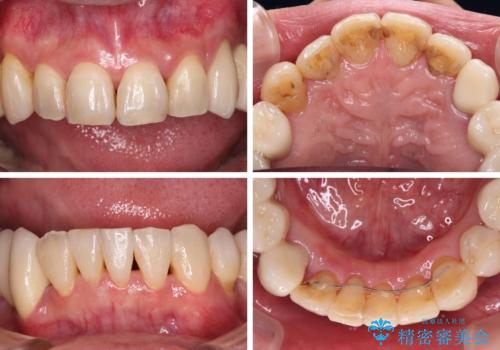

初診時に4年かかりますとお伝えし、実際に4年数ヶ月を要する治療となりました。

治療中は仮歯が頻繁に脱落したり、歯周外科によりむき出しとなった歯根が知覚過敏を起こしたりと、苦労は絶えませんでしたが、4年の治療の後にスッキリと仕上げることができました。